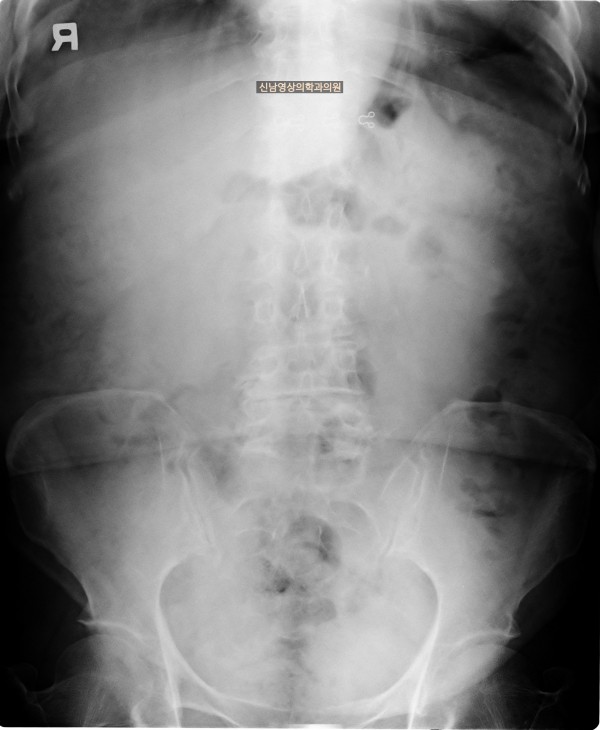

본 환자분은 변비가 지속되면서 좌하복부 통증이 있으셨던 분으로 본원에서 복부 초음파 검사를 진행하였습니다.

하행 결장 부위에서 장이 두꺼워진 소견이 보여 진행된 대장암의 가능성이 농후해보여 대학병원으로 전원해 대장내시경을 받고, 수술로 2기암으로 진단되신 케이스입니다.

평소에 일상생활에서의 지속되는 변비, 복통, 만져지는 혹이 있다면 복부 초음파 검사 및 대장내시경 검사를 받아보시는 것을 권유 드립니다 ~